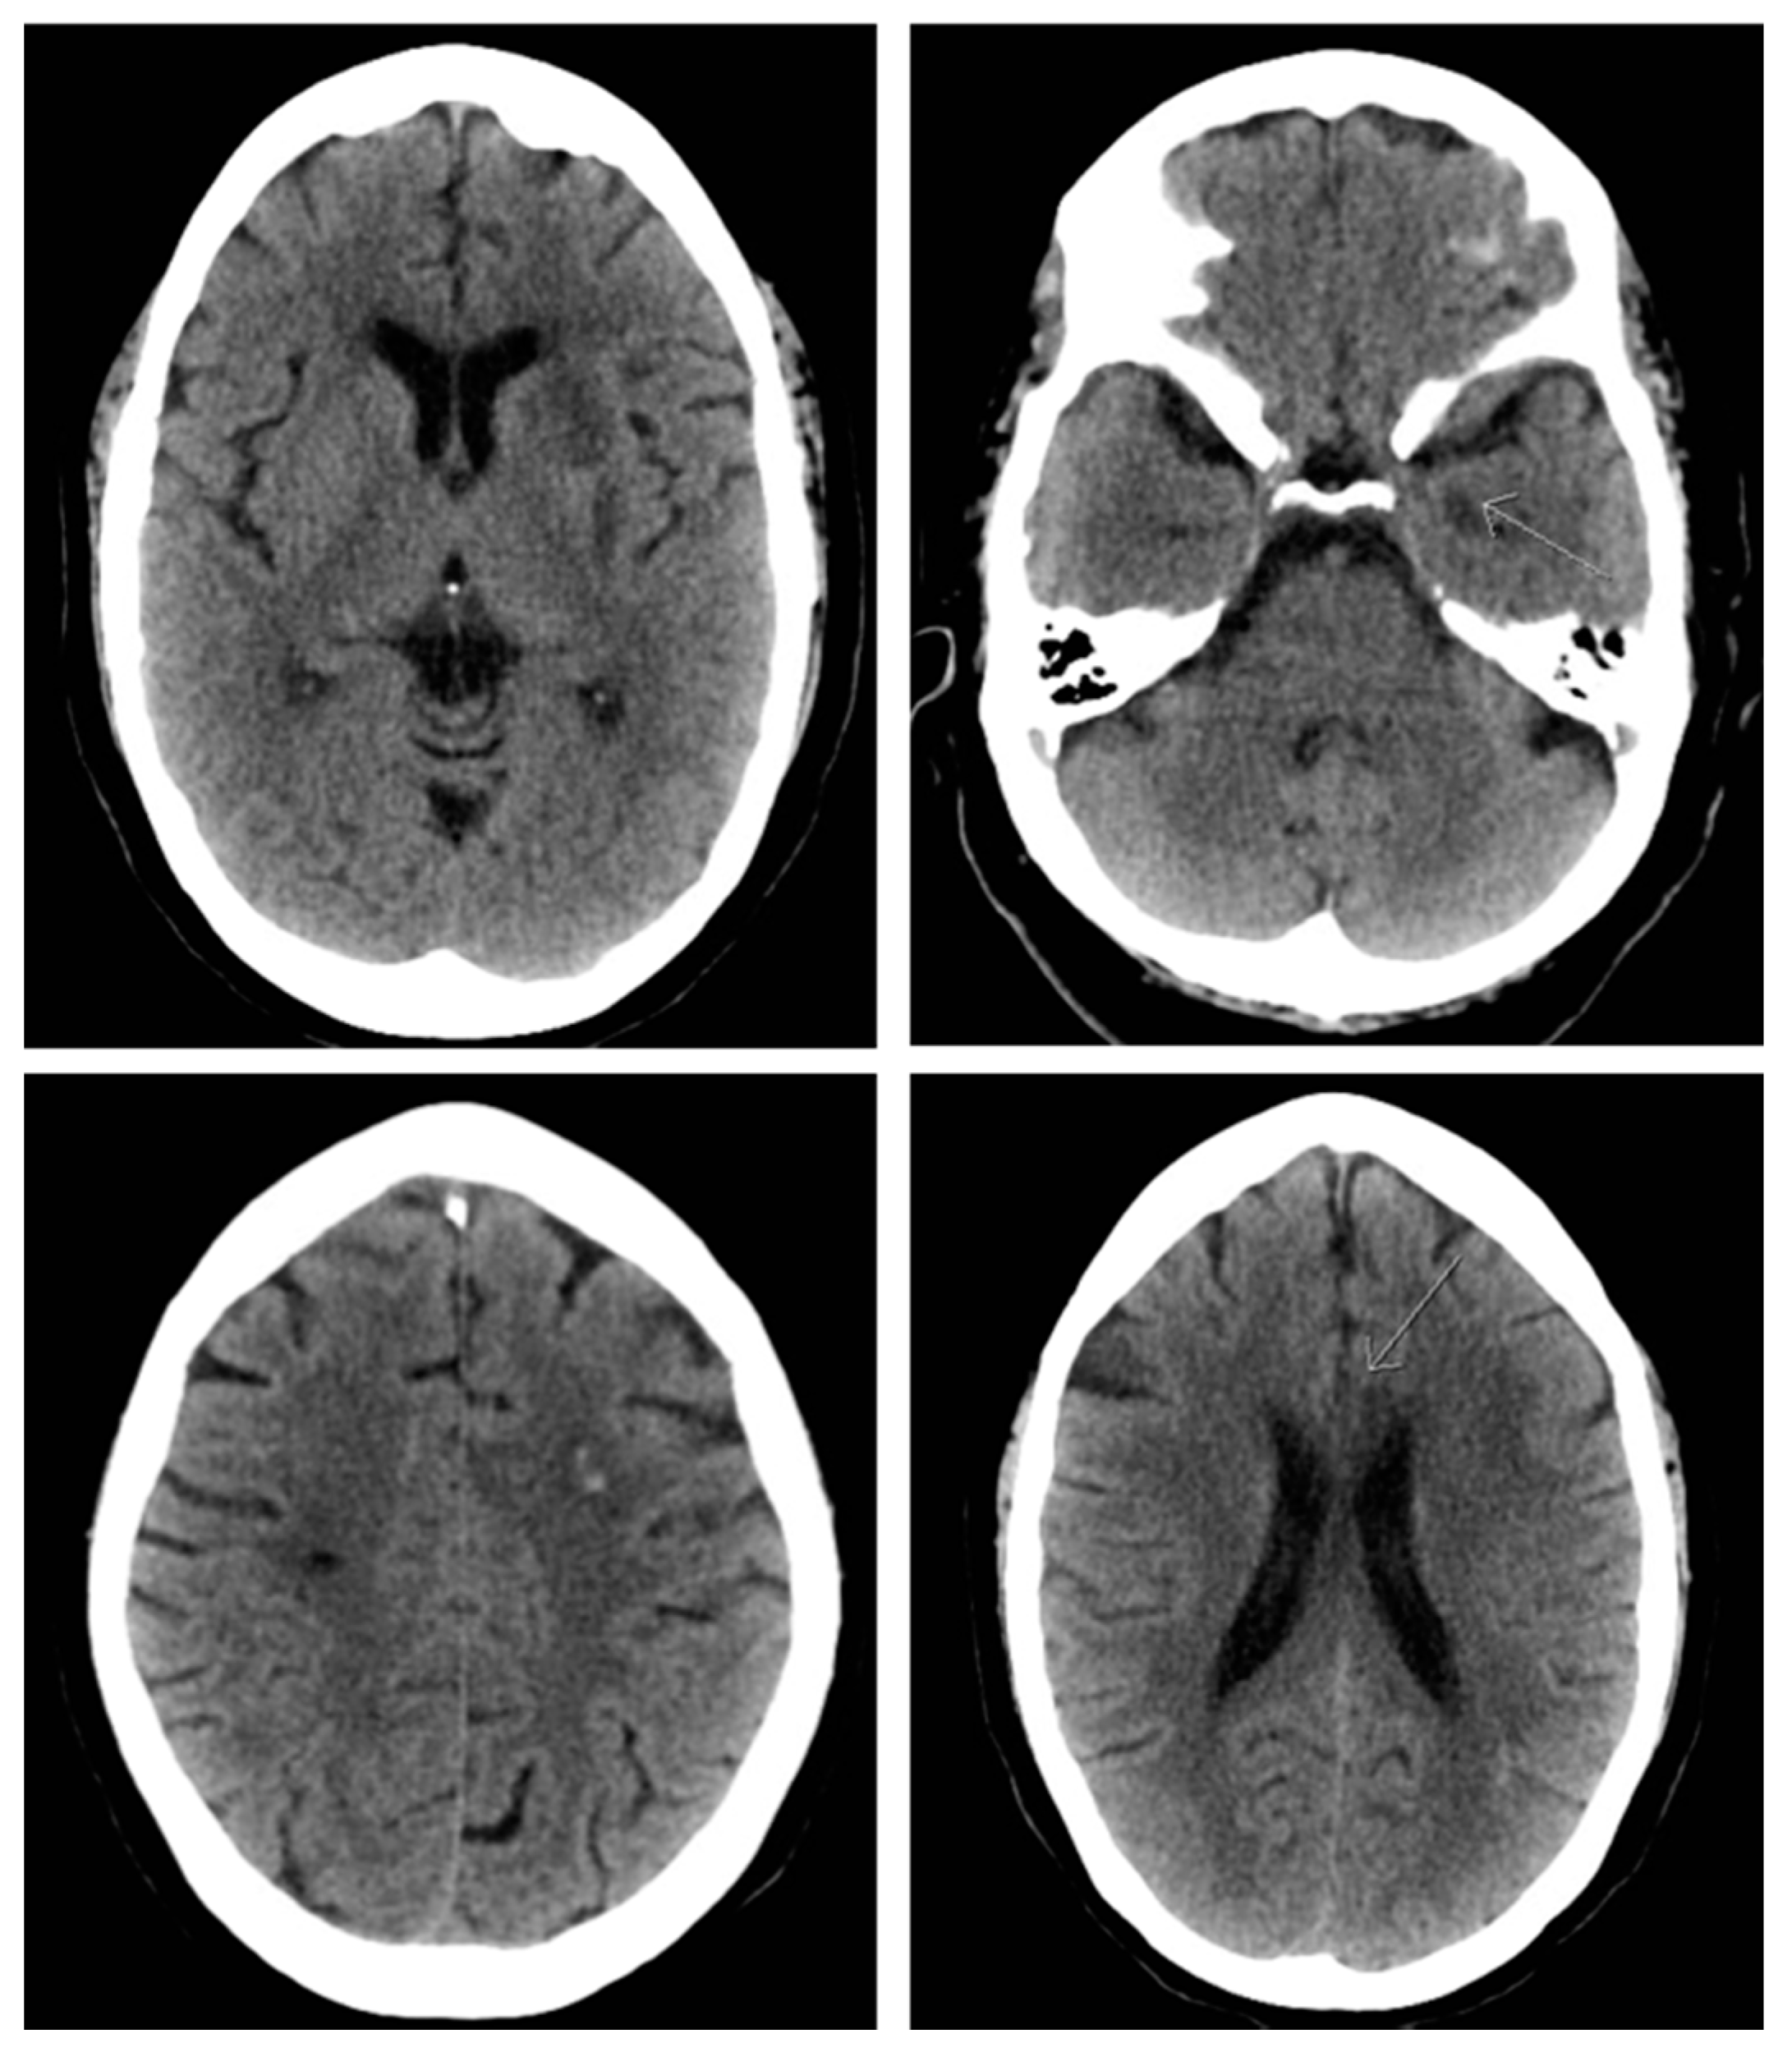

2. The Case